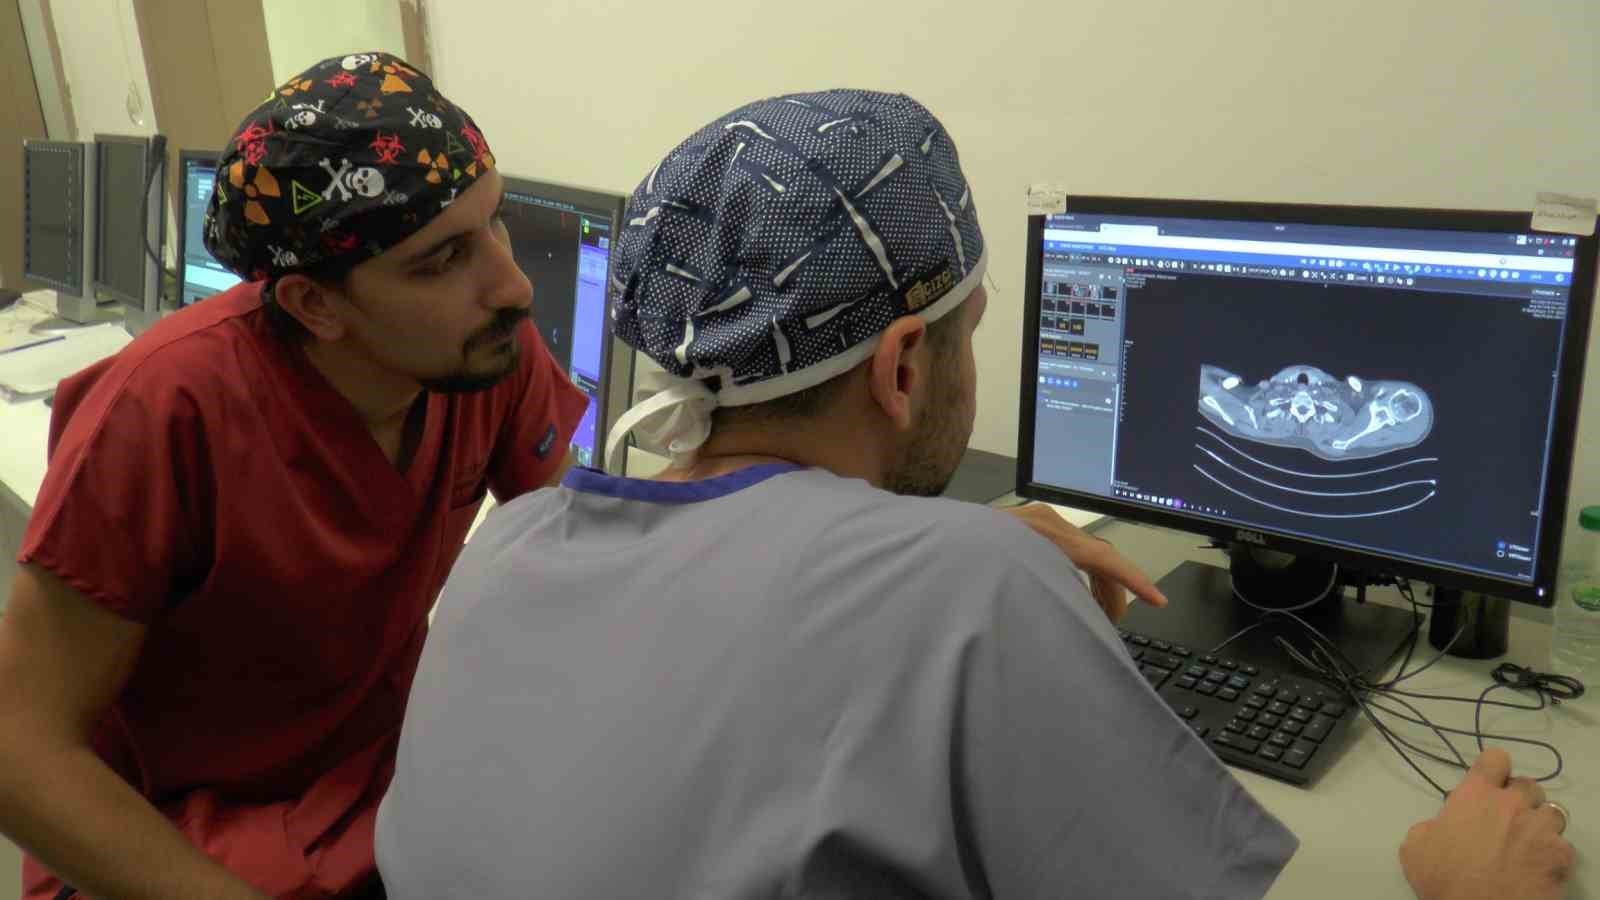

Kayseri'de yaşayan Behçet hastası Osman Turan, akciğerlerinde meydana gelen ve kendisinde ölüm korkusuna sebep olan kanamalardan Kayseri Şehir Hastanesi'nde uygulanan embolizasyon işlemi sayesinde kurtuldu.Behçet hastalığı bulunan Osman Turan'da hastalıkta nadir yaşanan bir durum görüldü. 'Hemoptiz' olarak adlandırılan durum sonucunda akciğerlerinde meydana gelen kanamadan dolayı ağzından ve burnundan kan gelen Turan, birçok kez kanamalarından dolayı yoğun bakımda yattı. Daha sonra Kayseri Şehir Hastanesi Girişimsel Radyoloji Bölümü'ne sevk edilen Osman Turan, hastanede uygulanan embolizasyon yöntemi ile kanamalarından ve yaşadığı ölüm korkusundan kurtuldu.Yaşanan durumun nefes sıkıntıları oluşturup arrest denilen ani kalp durmasına kadar gidebileceğini söyleyen Kayseri Şehir Hastanesi Girişimsel Radyoloji Bölümü'nden Dr. Sinan Karatoprak, "Behçet hastalığı Asya ülkelerinde ve bizim ülkemizde sık görülen romatolojik bir hastalıktır. Genellikle ağızda yaralar, genital bölgede ülserler ve nadiren de damar tutulumlarıyla seyreden romatolojik bir hastalıktır. Osman bey uzun süredir Behçet tanısı almış ve takipli olan bir hasta, ağzından akciğer kaynaklı kan gelmesi şikayeti ile göğüs hastalıklarına başvurmuştu. Orada çekilen tomografisinde kalpten kirli kanı temizlenmek üzere akciğere taşıyan damarda bir anevrizma dediğimiz baloncuk tespit edilmesi üzerine tedavi amaçlı bize yönlendirildi. Bu şekilde de işlem kararı verdik hastayla. Behçet hastalığında nörolojik tutulum ve vasküler tutulum nadir görülmekte. Özellikle Osman beyde olan durum hastalıkta yüzde 1 olarak tanımlanmıştır literatürde. Polimer arter anevrizma hastalarda en sık şikayet akciğerden kan gelmesi şikayetidir. Hemoptiz olarak adlandırıyoruz biz bu durumu ve bu durum aşırı miktarda kanama olduğu zaman hastada nefes sıkıntıları oluşturup arreste kadar gidebilir ki Osman beyde de geçmişte öyle bir durum olmuştu" dedi.Girişimsel Radyoloji Bölümü'nden Dr. Oğuz Aslan da Behçet hastalığı olanların kanama durumunda akciğer atardamarlarında bir anevrizma olabileceğini akıllarında bulundurması gerektiğini söyleyerek, "Osman bey bize göğüs hastalıkları tarafından yönlendirildi. Kendisinin Behçet hastalığı tanılı, tekrarlayan akciğer kaynaklı kanamaları mevcuttu ve pulmoner anevrizma dediğimiz bir baloncuk mevcuttu Behçet hastalığında sekonder olarak nadir gelişen bir durum olarak. Hastamıza bu anevrizmanın kapatılabileceğini ve işlemin nasıl olduğunu, risklerini anlattık. Kendisi de düşündü ve tedavi olmaya karar verdi. Öylelikle bir teşhise dair anjiyoya aldık kendisini. Tedavi planımızı belirledik ve ikinci bir seansta kendisine bu büyük damarları tıkamakta kullandığımız vasküler tıkaçlar dediğimiz materyaller ile anevrizmasını kapattık. Anevrizma kapatmanın aslında birçok yöntemi var ama hastamızın besleyici damarı çok büyük olduğu için bunları daha büyük damarları tıkamak için kullandığımız materyalleri kullandık. Bir gün serviste yattı ve ertesi gün taburculuğunu sağlamış olduk. Bizim gördüğümüz hastaların çoğu Behçet hastası ve bu hastaların yüzde 1-2'sinde görülebiliyor bu komplikasyon. Embolizasyon işlemi sonrasında hastamızın bu mevcut durumu tamamen kapandığı için en azından bu anevrizma özelinde ekstra bir akciğer kanaması hemoptizi ihtimali ortadan kalkmış oldu. Şöyle söyleyebiliriz; Behçet hastalığı tanısı olan hastaların öksürükle ağzından kan gelmesi durumunda akciğer atardamarında bir anevrizma olabileceği akılda bulundurulmalı ve bunun tedavisi için gerekli başvurular da yapılmalıdır. Burada hastalar Girişimsel Radyoloji Kliniği'ne de başvurabilirler ya da göğüs hastalıkları tarafından da bize yönlendirilebilirler" ifadelerini kullandı."Kanamalardan dolayı korkarak yaşıyordum"Kanamalardan dolayı korkarak yaşadığını ve daha önce ölümden döndüğünü söyleyen Osman Turan ise, "Ben kendimi bildim bileli Behçet hastasıyım. Bunun için de Kayseri Şehir Hastanesi Göğüs Hastalıkları'nda her zaman tedavi görmekteydim. Benim akciğerlerimde hemoptiz kanama oluyordu ve bunun geçebilmesi için. Oradan beni Girişimsel Radyoloji bölümüne yönlendirdiler ve geldim burada tedavilerim yapıldı. Benim akciğerlerimdeki kanamanın durdurulabilmesi için yani baloncuğun kapatılabilmesi için tedavi yöntemlerini söylediler. Sonrasında tedavim yapıldı. Şimdi de şükürler olsun hiçbir kanamam yok. İnşallah da olmaz bundan sonra. Ben bu sebepten korkarak yaşıyordum. Çünkü yolda giderken, evde otururken hatta yemekte dahi ağzımdan kan gelemeye başlıyordu ve direkt hastaneye yetişmek zorunda kalıyordum. Çok kez yoğun bakımlarda yattım ama şimdi öyle bir şeyim yok şükürler olsun iyiyim, artık kan da gelmiyor. Bir gün dışarıda ağzımdan ve burnumdan kan gelmeye başladı. Baygınlık geçirmeye başladım. Ambulansın gelmesi için dua ediyordum. Baygınlık geçirirken kendimi öldüm sandım. Ölmedim ama ölümden döndüm. Ameliyatım bittikten sonra "Başardık, bitirdik" dediler. İşlemi tamamladıklarını gösterdiler. Ben de o heyecanı duyunca çok sevindim. İnşallah benim gibi Behçet hastası olan kişilere umut olurlar bundan sonra da ve tekrar böyle şeyler yaşanmaz. Behçet hastasının akciğerden kanaması ile ilgili olan ölümü duymayalım" dedi. İHA

Akciğerlerindeki ölümcül kanamalarından 'Embolizasyon' işlemi sayesinde kurtuldu

Kayseri'de yaşayan Behçet hastası Osman Turan, akciğerlerinde meydana gelen ve kendisinde ölüm korkusuna sebep olan kanamalardan Kayseri Şehir Hastanesi'nde uygulanan embolizasyon işlemi sayesinde kurtuldu.